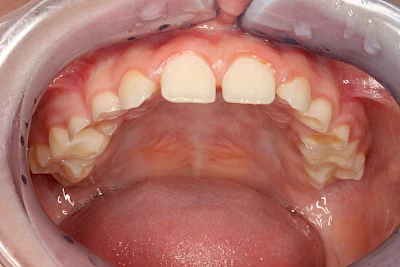

Keilförmiger Defekt

Eine Sonderform sind sogenannte keilförmige Defekte im Bereich der Zahnhälse. Hier geht man davon aus, dass Knirschen und Pressen in Kombination mit falschen Putzgewohnheiten (zu hoher Putzdruck, Verwendung von Zahnpasta mit hohen Abrasionswerten) eine Rolle spielen.